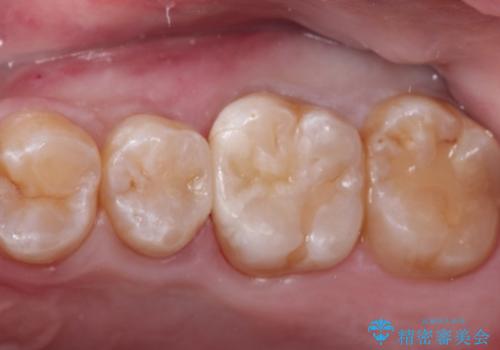

臼歯 咬合の再構成

担当医 大元洋佑